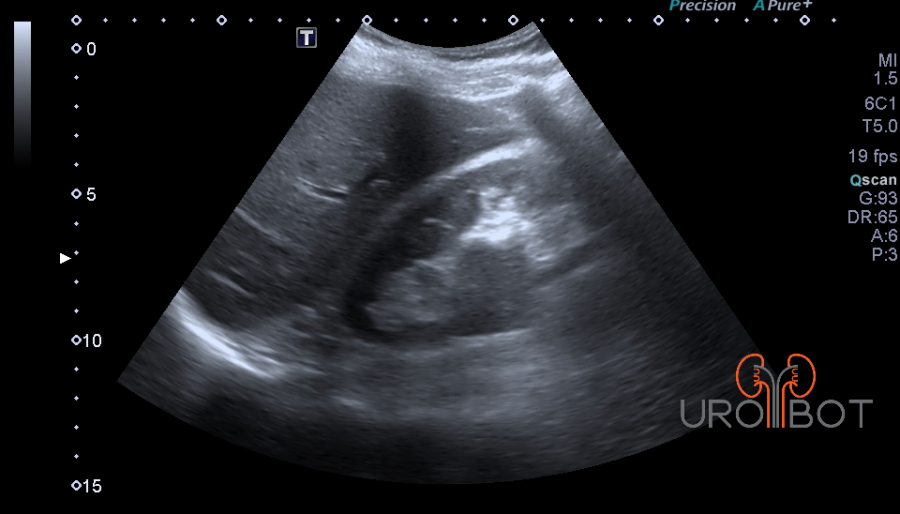

Video Tumorthrombus von Dr. Müller

Das Video zeigt eine sonographische Untersuchung der rechen Seite mit Nachweis eines großen Tumorthrombus in der unteren Hohlvene.